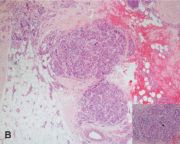

| 06:08, 31 באוקטובר 2023 | Myocarditis3.jpg (קובץ) |  |

130 קילו־בייטים | Motyk | 1 | |

| 14:51, 30 באוקטובר 2023 | Myocarditis2.png (קובץ) |  |

64 קילו־בייטים | Motyk | 1 | |

| 13:08, 30 באוקטובר 2023 | Myocarditis1.png (קובץ) |  |

235 קילו־בייטים | Motyk | 1 | |

| 12:06, 30 באוקטובר 2023 | Myocarditis4.jpg (קובץ) |  |

142 קילו־בייטים | Motyk | 1 | |